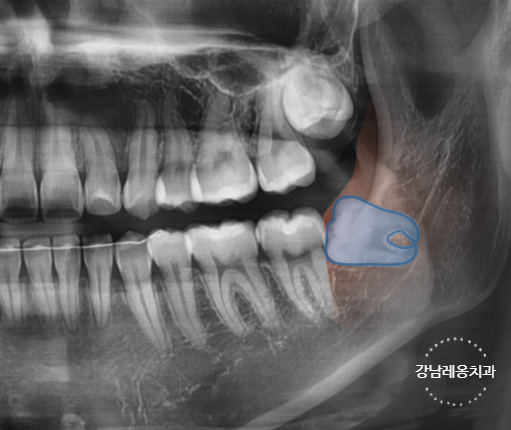

✅ 잇몸 속에 완전히 묻혀 있는

완전 매복 사랑니

✅ 옆으로 누워있는 수평 매복 사랑니

✅ 아래턱 신경과 매우 가까운 위치의 사랑니

✅ 뿌리가 휘어있거나 여러갈래로 나뉜 사랑니

✅ 염증이나 낭종을 동반된 경우

고난도 케이스 경험 다수

최소절개

하루 발치 최대 60개

사랑니 발치로 강남레옹치과에 방문해주시는

40~50%가 수평/매복 사랑니이며

아래와 같은 고난도 케이스도

충분한 상담을 통해

사랑니 진료를 진행하고 있습니다.